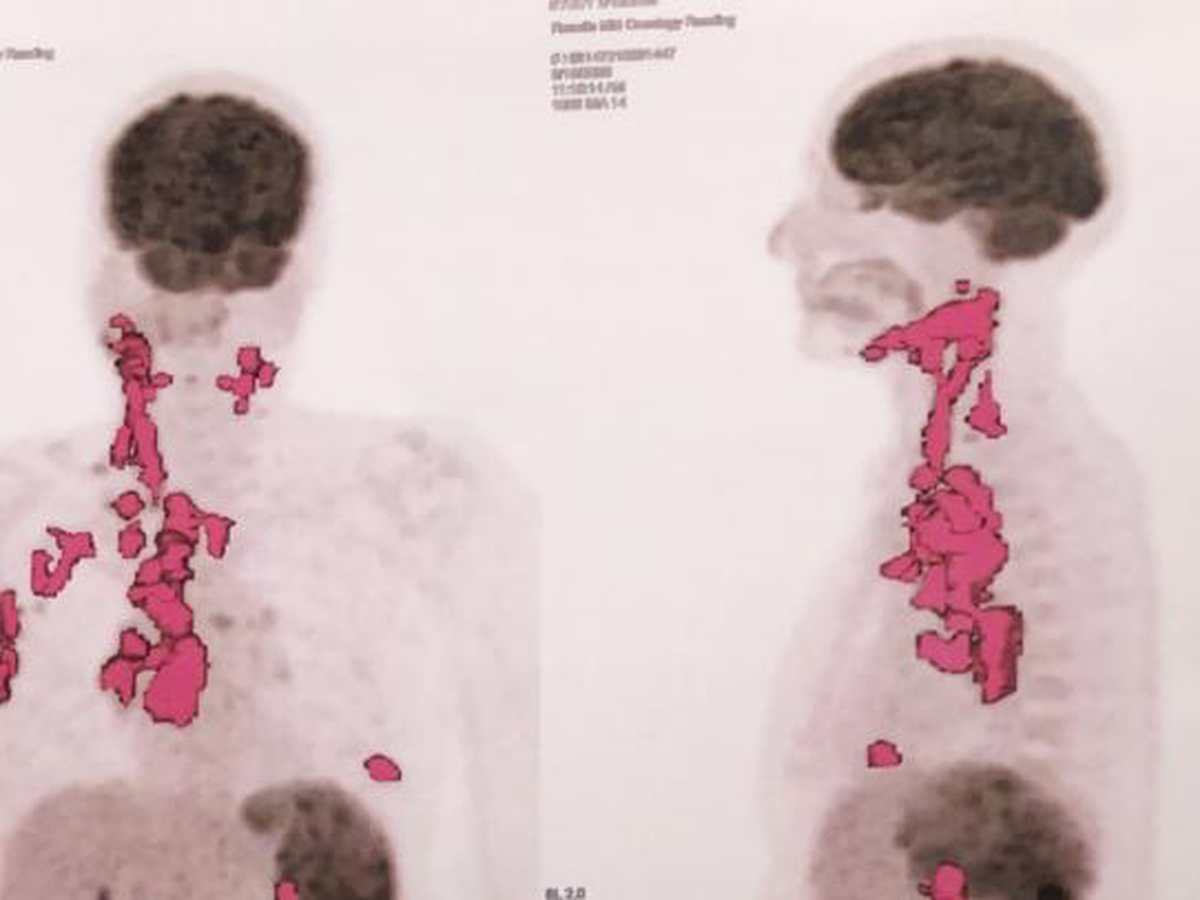

Je m’appelle Hajar, je vis et travaille à Montréal, mais ma maman, qui ne vit pas avec moi, traverse une période très difficile. Elle a été diagnostiquée avec un lymphome de Hodgkin de stade 3, une maladie grave qui nécessite un traitement coûteux : médicaments, examens et séances de thérapie. Malheureusement, ces frais sont un fardeau trop lourd pour notre famille.

My name is Hajar. I live and work in Montreal, but my mother, who doesn’t live with me, is going through a very difficult time. She has been diagnosed with stage 3 Hodgkin’s lymphoma, a serious illness that requires expensive treatment, including medication, tests, and therapy sessions. Unfortunately, these costs are an overwhelming burden for our family.